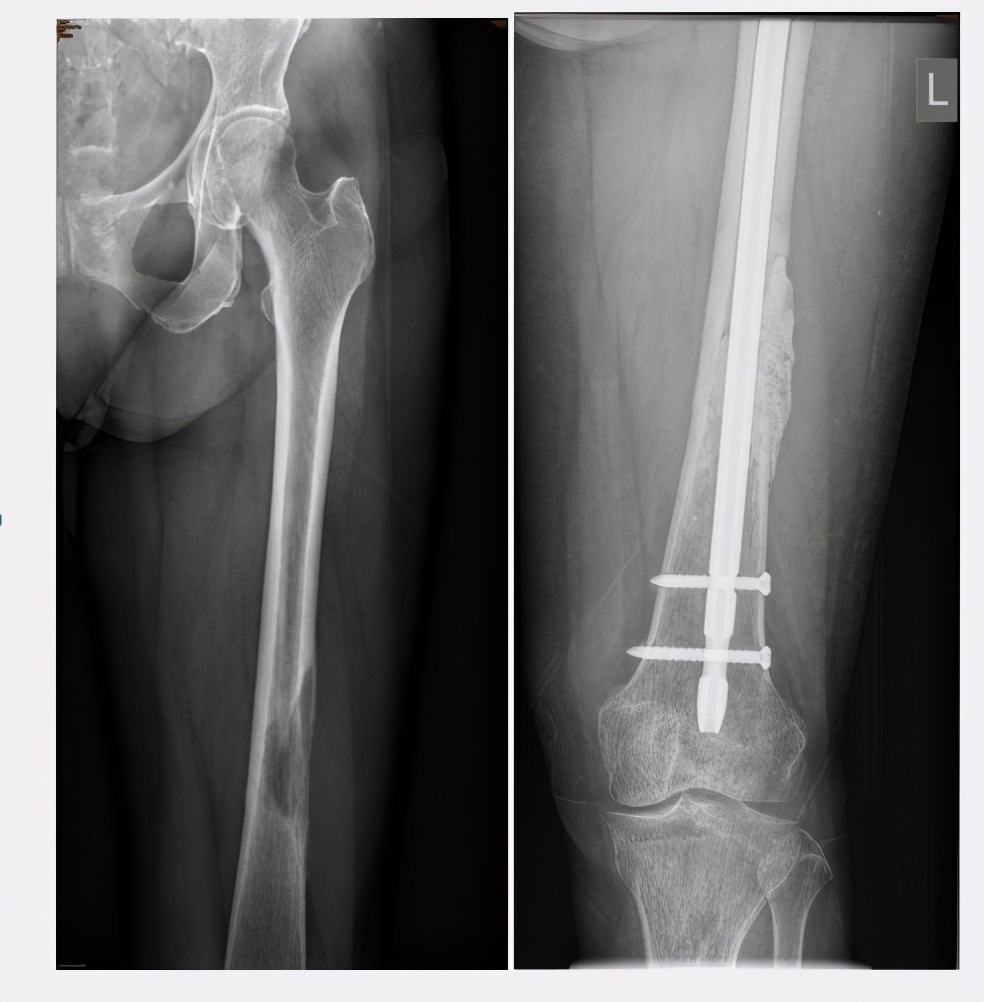

1.当癌细胞转移到四肢,病灶大于2.5厘米,病变破坏范围超过骨皮质50%,且患者出现完全性的骨质溶解时,可采取“肿瘤灭火+内固定、假体置换“的方法,对患者进行治疗。